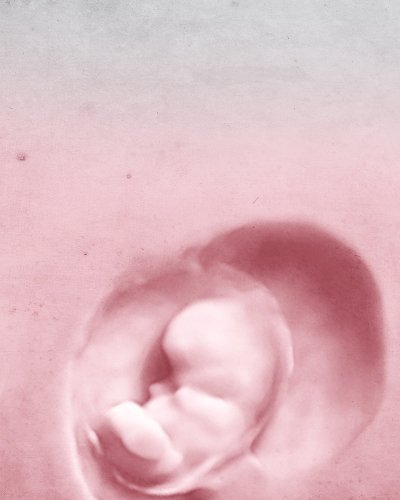

Мы поможем создать семью

ИНДИВИДУАЛЬНОЕ ИССЛЕДОВАНИЕ РОДОВОДНОСТИ ДЛЯ ИНДИВИДУАЛЬНОГО ЛЕЧЕНИЯ